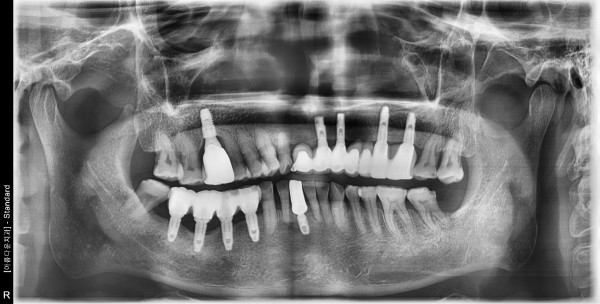

62세 남/ 아래 앞니 발치 후 임플란트 즉시식립